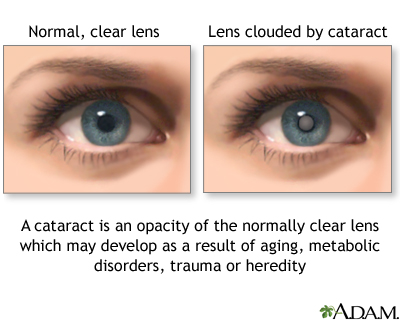

Rubella is caused by a virus. The infection leads to a mild illness that includes a rash, enlarged lymph nodes, and sometimes a fever. If a pregnant woman is infected during her first trimester, her baby has an 80% chance of developing birth defects, including heart abnormalities, cataracts, deafness, and learning disabilities.